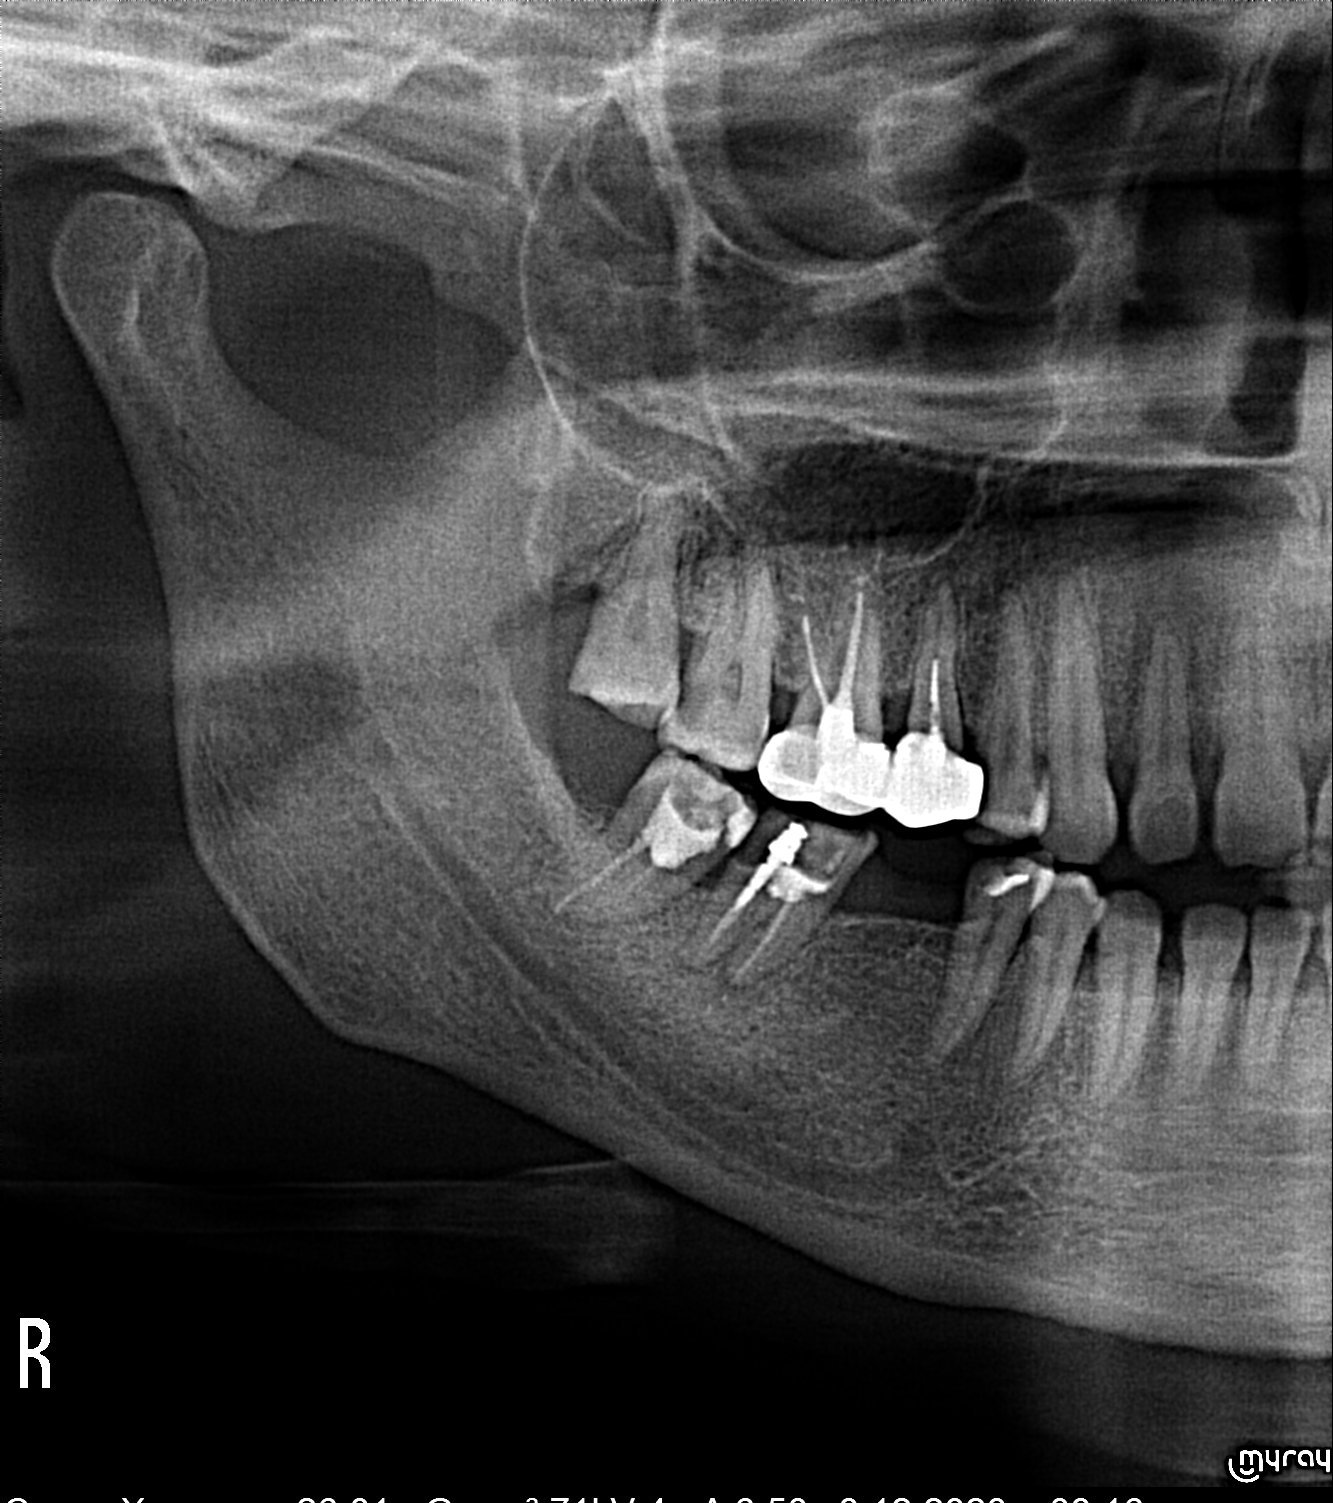

Здравейте. От неделя съм със силна болка в долен втори зъб (на снимката е със щифта)и съм на болкоуспокояващи. Болката е при натиск. Зъбът е лекуван през август месец. Според зъболекаря не се вижда видим проблем. Видя се проблем във горен втори зъб, където имало голям кариес на който сложи лекарство. Според вас виждали се проблем на зъбът, който ме боли? Болката не е намаляла след поставяне на лекарство на горния зъб, и ще минавам на антибиотик😥